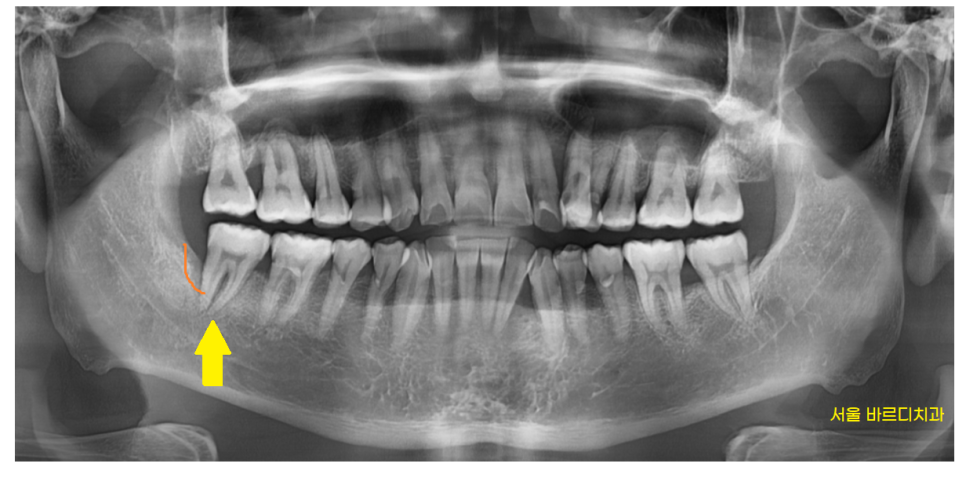

230915

6개월 뒤 덕풍동 치과 내원해주신 사진입니다.

잇몸치료를 계속 받고 있는 상황이었지만

잇몸 뒤쪽 뼈가 더 녹아있습니다.

ct 상에서 잇몸 뼈 한쪽이

움푹 패여졌네요.

뼈가 많이 녹아

치아 뿌리를 붙잡고 있는게 얼마 없다보니

잇몸 욱신 욱신

느끼셨던것 같습니다.